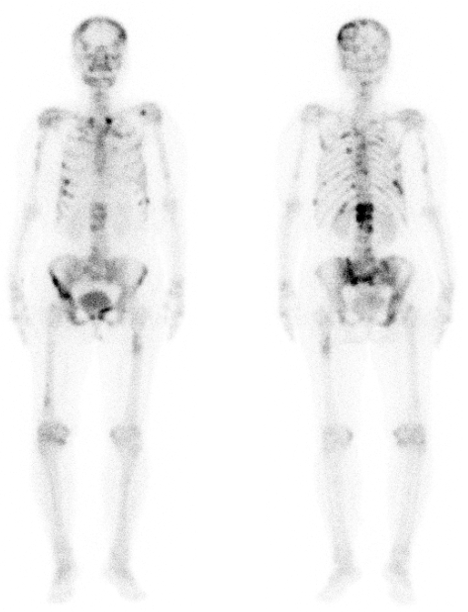

为满足临床诊疗需求,现开展全身骨扫描、甲状腺显像及全身碘扫描等检诊项目。其中全身骨显像是核医学最常用的检查项目之一,在恶性肿瘤(尤其是乳腺癌、前列腺癌、肺癌等)骨转移的筛查中发挥了不可替代的作用;甲状腺显像及全身碘扫描作为特异性显像手段,应用于分化型甲状腺癌患者术后131碘的治疗中,在甲状腺癌残留病灶及转移灶的检出中有其他检查方式不可比拟的优势。

图例1:患者,女,54岁,左侧乳腺癌术前,行全身骨扫描发现全身多发骨转移。